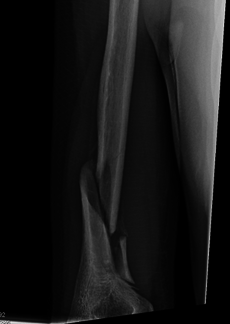

![]() Holstein–Lewis fracture at 5 weeks post fracture | |

A Holstein–Lewis fracture is a fracture of the distal third of the humerus resulting in entrapment of the radial nerve.